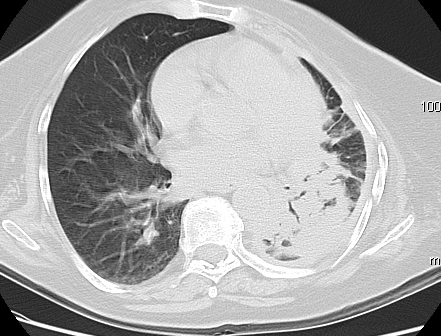

Foto: Aleksandar Ivković Foto: Aleksandar Ivković Foto: Aleksandar Ivković Strašna razlika kod pluća pušača i kovid pozitivne osobe autor: Božica Luković Zdravlje 23. jan. 2021. 12:06 > 23. jan. 2021. 12:15 0 Podeli vest: Radiolog Aleksandar Ivković od početka pandemije daje korisne informacije o svim aspektima kovida 19. On je nedavno uporedio rendgen snimke pluća zdrave osobe, pušača, osobe koja je zaražena gripom H1N1, a onda i osobe koja ima kovid 19. Razlike su zapanjujuće. Podeli vest: Oglas Objavu doktora Ivkovića sa njegovog bloga "Ljudi i ostale laži" prenosimo u celosti."Nedavno sam video u medijima da je neko preneo rdg sliku i razlike kod nalaza zdrave osobe, pušača i bolesnog od kovida 19. Kako nisam baš previše zadovoljan onim što je prikazano, evo kako to izgleda u našoj varijanti. Zdrava osoba CT nalaz kod zdrave osobe podrazumeva da ne postoje nikakvi poremećaji strukture plućnog parenhima, da su krvni sudovi uredni i da nema suženja disajnih puteva, kao i da nema uvećanih limfnih žlezda u hilusima pluća i medijastinumu. Foto: Aleksandar Ivković | Foto: Aleksandar Ivković * Foto: Aleksandar Ivković | Foto: Aleksandar Ivković Zdrava muška osoba mesec dana nakon zapaljenja pluća tokom kovida 19. Nalaz bez nekih posebnih problema iako se naziru tragovi zapaljenja. Snimak u boji je zdrava osoba, nepušač, bez ikakvih bolesti pluća u istoriji. Grip H1N1 Pokazaću samo drastične nalaze kod gripa H1N1, to je znači onaj grip koji je izazvao epidemiju španske groznice i epidemiju 2009. godine koja još uvek nije prestala (svake godine imamo makar 15%). Foto: Aleksandar Ivković | Foto: Aleksandar Ivković * Foto: Aleksandar Ivković | Foto: Aleksandar Ivković * Foto: Aleksandar Ivković | Foto: Aleksandar Ivković * Foto: Aleksandar Ivković | Foto: Aleksandar Ivković Nisu svi pacijenti imali ovakve nalaze, pokazujem one koji su imali tešku kliničku sliku. Kod gripa se sve odvija obično u sedam dana. Kao što se vidi, zapaljenje je bilo jednostrano, uglavnom. Ali kada je dolazilo do pogoršanja, onda je centralno obostrano dolazilo do edema pluća. Pušenje Kod pušača postoje razne varijante nalaza na plućima. U principu nisu tako dramatične kao što su zapaljenja. Nalaz na plućima kod pušača može biti potpuno normalan. Ovo ne pišem zato što podržavam pušenje, naprotiv, veliki sam protivnik, ali iznošenje laži nikada nije dobro. Dve dijagnoze su bitne kao posledica pušenja. Prva je hronična plućna opstruktivna bolest: Foto: Aleksandar Ivković | Foto: Aleksandar Ivković * Foto: Aleksandar Ivković | Foto: Aleksandar Ivković * Foto: Aleksandar Ivković | Foto: Aleksandar Ivković Jasna je razlika u nalazu, posebno na ovim slikama u boji, gde su ta plava polja delovi pluća koji su propali zbog cigareta (može da se uporedi sa zdravim plućima iznad).Druga bolest koja je česta kod pušača je u svakom slučaju karcinom. Foto: Aleksandar Ivković | Foto: Aleksandar Ivković * Foto: Aleksandar Ivković | Foto: Aleksandar Ivković * Foto: Aleksandar Ivković | Foto: Aleksandar Ivković * Foto: Aleksandar Ivković | Foto: Aleksandar Ivković Tkivo koje raste unutar pluća i razjeda ga. Takav je nalaz kod karcinoma pluća. Često je uzrok upotreba cigareta. Kovid 19 O kovidu sam pisao puno puta. Evo nekih slika, radi poređenja. Foto: Aleksandar Ivković | Foto: Aleksandar Ivković * Foto: Aleksandar Ivković | Foto: Aleksandar Ivković * Foto: Aleksandar Ivković | Foto: Aleksandar Ivković * Foto: Aleksandar Ivković | Foto: Aleksandar Ivković Nakon što pacijent bude izlečen od gripa ili kovida 19, pluća se mogu vratiti u normalu.To je razlika u odnosu na posledice upotrebe cigareta. Ovi snimci nisu postavljeni da bi se poredile bolesti, već da bi se ukazalo kako različite bolesti deluju na pluća. I ono što je veoma važno, ako neko dobije jednu od ovih bolesti, ne znači da u toku života neće dobiti drugu.Ne pišem zato smo smatram da sam najpametniji ili najpozvaniji da objašnjavam, nisam kao neki pojedinci ubeđen da samo ja imam znanje i istinu, pišem jer drugi ćute. Pišem jer ima i puno onih koji iznose laži, mora se tome stati na put.A ovi, koji pišu da sam umro, da sam oboleo od karcinoma, ovi koji mi žele da nađem dobro grobno mesto, šta da vam kažem, vi ste mi inspiracija. Svesni ste da sam u pravu i odlično znam da ste već uradili sve da se vakcinišete i mnogi od vas će to uraditi pre mene ali i dalje ćete ubeđivati druge da se ne vakcinišu i da je dobro za njih da se razbole i umru. Ima puno reči za vas u svim našim slovenskim jezicima, znate vi sami šta ste", piše dr Ivković.***Bonus video:https://youtu.be/MWucTT0qBsIPratite nas i na društvenim mrežama:FacebookTwitterInstagram Dr Lukić otkrio spisak svih antibiotika za kovid upalu pluća Zdravlje 0 Dr Žujović: Kako oporaviti pluća posle korone Zdravlje 0 Pet znakova da ti je kovid zahvatio pluća Zdravlje 0 Virusolog Ana Banko ruši veliku zabludu o ruskoj vakcini Emisije 0 aleksandar ivković korona kovid pluća snimak pluća Pratite nas na društvenim mrežama: Koje je tvoje mišljenje o ovoj temi? Učestvuj u diskusiji ili pročitaj komentare Budite prvi koji će ostaviti komentar Pošalji komentar Pročitaj komentare (0)